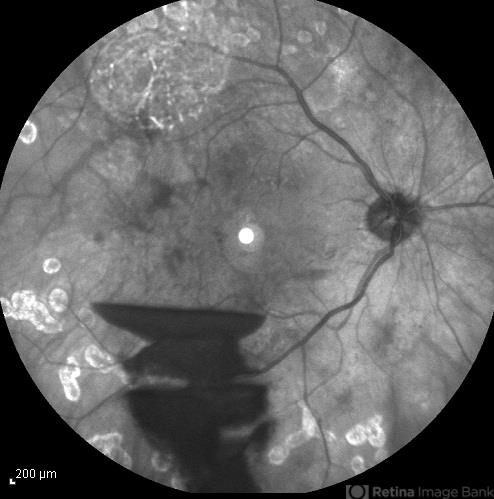

- infrared image, preretinal hemorrhage

- Hamid Ahmadieh, MD, Ophthalmic Research Center, Labbafinejad Medical Center, Shahid Beheshti University of Medical Sciences

- Heidelberg HRA

- Infrared image of a 30-year-old woman with the history of scatter laser photocoagulation and a preretinal hemorrhage due to active PDR .